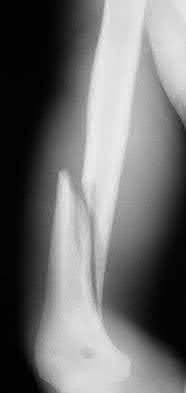

Figure A shows a radiograph of a 19-year-old male with an isolated shotgun injury. On physical examination, he has a 3 cm wound over the posterolateral aspect of his arm. In addition, he has weakness with wrist and finger extension, but no sensory deficits. The patient has received tetanus prophylaxis and antibiotics in the emergency department. What would be the next best steps in treatment?

This patient has sustained a shotgun blast to the midshaft humerus. The next best step would be irrigation and debridement, and external fixation of the fracture.

Shotgun injuries are typically treated as open fractures, whereas low-energy gunshot wounds are treated as closed fractures. The initial operative treatment of shotgun wounds should include irrigation and debridement and stabilization with external fixation. The goal of treatment is to stabilize the severe soft-tissue injury and bone loss, as well as to aggressively debride devitalized tissue and gross contamination.

Dougherty et al. reviewed gunshot fractures to the humerus. They report that

peripheral nerve injuries are relatively common with these injuries, with a more common incidence in distal injuries than proximal.

Figure A shows a high velocity shotgun fracture to the left humerus with retained buck fragments. Illustration A shows a similar injury stabilized with external fixation.